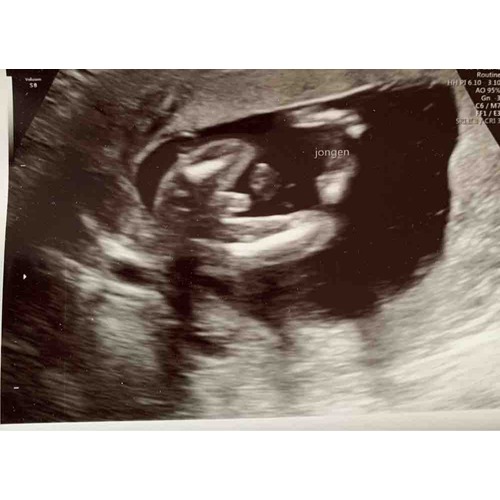

Je ziet op de onderste twee bovenbenen en een piemel. Ik vind het wel lastig te zien. Foto is nog ver weg. Dit was mijn echo met een jongen bij 16weken, misschien kan je het een beetje vergelijken met de onderste echo.

Ik ben ook bij pretecho en zo geweest met 14 weken. Bij mij was duidelijk dat het een jongetje wordt. Nu middels bijna 22 weken, op de 20 weken echo kreeg ik idd de bevestiging dat we een zoontje krijgen. Je zag duidelijk het piemeltje op de 14 weken geslachtsecho, het kon niet mis zijn!